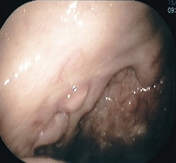

図1:右扁桃にできたがん

中咽頭とは口を開いて覗き込むと見ることができる「のど」の部位のことです。その中には扁桃(腺)や舌根(舌の根元)、口蓋垂(のどちんこ)などがあります(図1)。そこにできるがんを中咽頭がんと呼びます。中咽頭がんの原因には多量の喫煙や飲酒が古くから知られています。最近になり、その他の原因としてヒトパピローマウイルス(HPV)が関与していることが分かり、日本でも中咽頭がんの約半数でHPVが原因のがんであることが分かってきています。